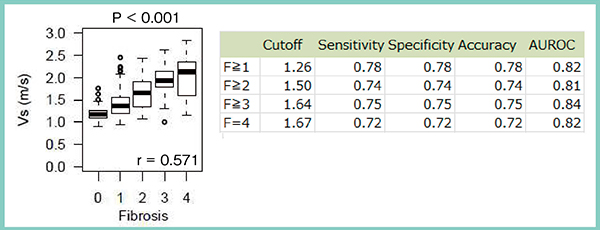

対象は,2015年7月〜2017年3月に肝生検を施行した慢性肝疾患353名,臨床的肝硬変13名,健常者22名の計388名で,肝生検と同時にSWMおよびRTEを実施した。病理所見による線維化ステージは,線維化なし(F0)が55名,軽度の線維化(F1)が182名,肝硬変(F4)が32名であった。SWMのVs値と病理所見を比較すると,線維化の悪化に伴いVs値が上昇する明らかな相関が見られ(図2),線維化の程度を非侵襲的かつ定量的に予測可能であった。肝硬変におけるVs値のカットオフ値は1.67m/sで,前述の症例は2.06m/sであることから肝硬変であると推測できる。さらに,SWMとRTEの計測値を基に,線維化を推定するfibrosis index(F index)と炎症を推定するactivity index(A index)を算出し,病理所見と比較したところ,やはり線維化ステージの上昇に伴いF index,A index共に上昇した(図3)。

図2 SWMのVs値と病理所見による線維化ステージとの比較